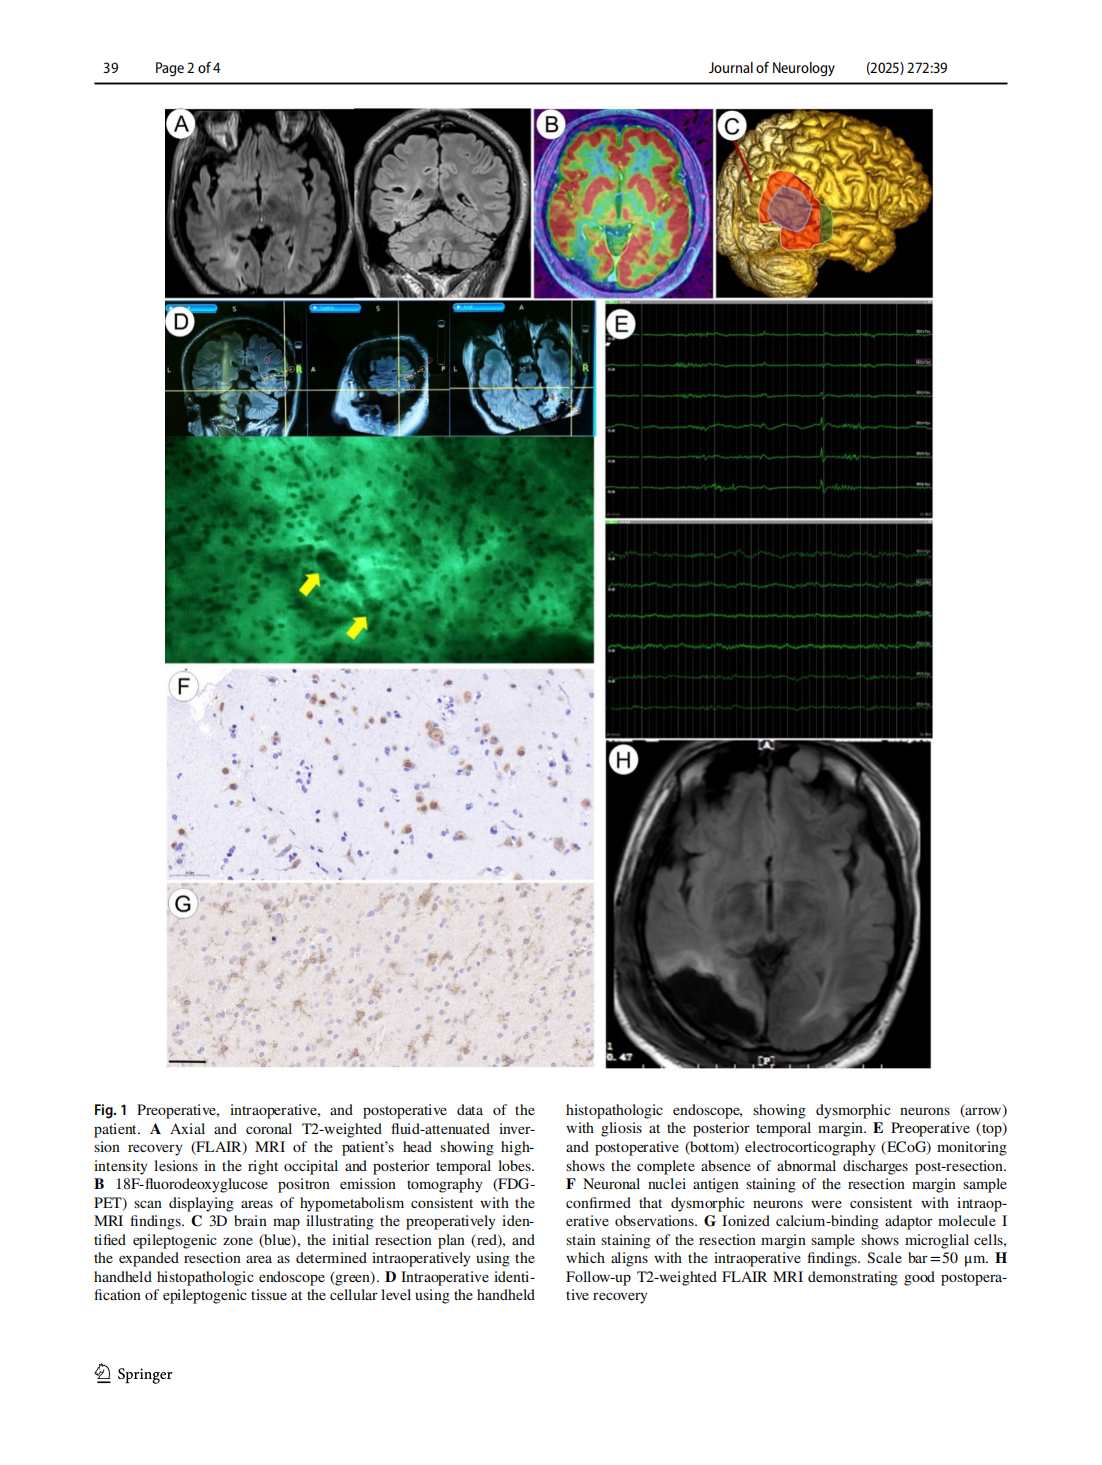

Intraoperative identification of?epileptogenic foci using handheld histopathologic endoscopy: a?case report